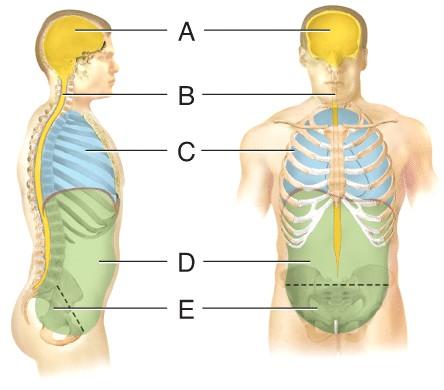

Name the cavity A.

dorsal

cranial

vertebral

ventral

cranial

Name the cavity C.

cranial

thoracic

abdominal

pelvic

thoracic

Name the cavity formed by A and B.

abdominopelvic

ventral

dorsal

pelvic

dorsal

Name the cavity formed by D and E.

ventral

abdominopelvic

dorsal

thoracic

abdominopelvic

Name the cavity formed by C, D and E.

dorsal

cranial

ventral

abdominopelvic

ventral

Name the cavity E.

cranial

pelvic

abdominal

thoracic

pelvic